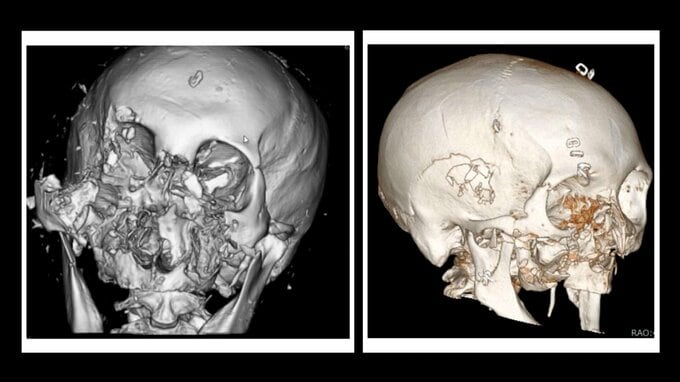

クマに襲われた患者のCT画像では、顔の骨が激しく砕けているのが分かります。

負傷者の9割が顔面に深い傷を負うというクマ外傷。あごや鼻の骨が折れたり、顔が引き裂かれたり。

クマの攻撃で傷を負った部位のうち、顔面が90%、続いて腕70%、頭部60%、脚40%と上半身が圧倒的に多くなっています。